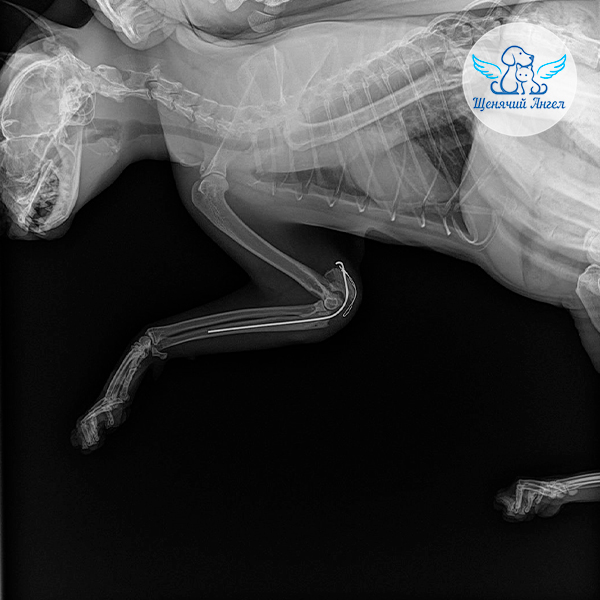

🩻 Рентген выявил перелом правой локтевой кости и пулю! в мягких тканях лапы. Врачи оперативно приняли решение о хирургическом вмешательстве: выполнили остеосинтез, восстановили положение костных отломков и зафиксировали их ❤️‍🩹.

Через три недели Джокер стал сильно хромать, и контрольный снимок показал, что фиксирующая спица сместилась 😔. Такое иногда случается при активных движениях у хвостиков в период восстановления, так как ткани и кости продолжают перестраиваться.

Джокеру провели повторную операцию. Она прошла успешно, и на этот раз костные структуры зафиксировали более надёжным методом ☝🏻.